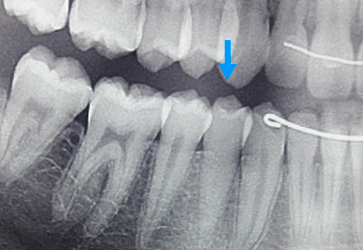

Radiograficamente visualiza-se uma obliteração parcial ou total do espaço pulpar.